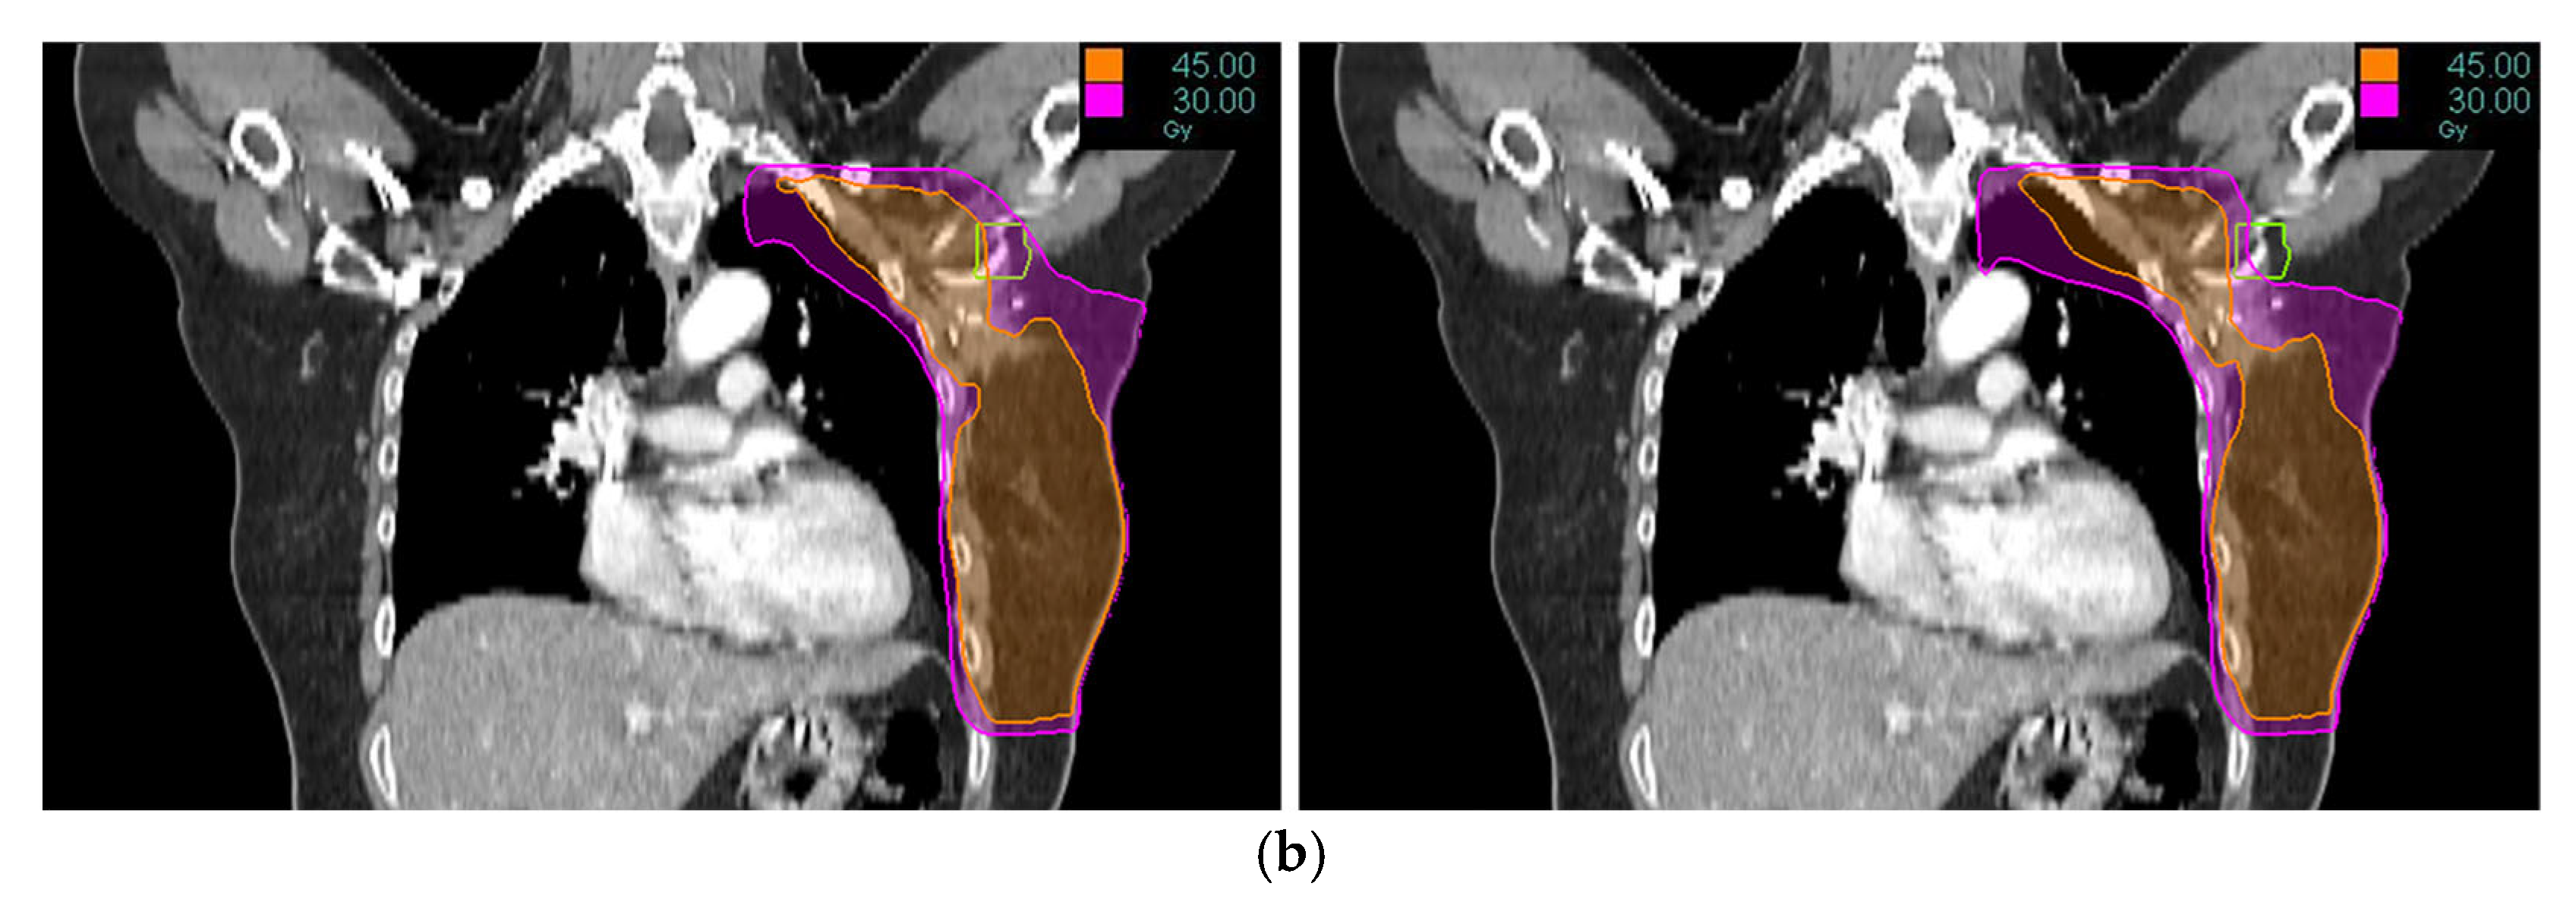

Tomotherapy plan images along with the DVH of a typical patient is illustrated in Figure 1 and Figure 2. The newly generated plans, successfully optimized to meet all standard dose-volume constraints for both target volumes and standard OARs, achieved significant sparing of the ALTJ without compromising the dose received by other critical OARs.

Figure 1. Tomotherapy plan image of a typical patient: (a) axial view, (b) coronal view. The contoured ALTJ (green) is shown, and the dose distributions with isodose lines (30 and 45 Gy) compared between conventional (left) vs. study plan (right).